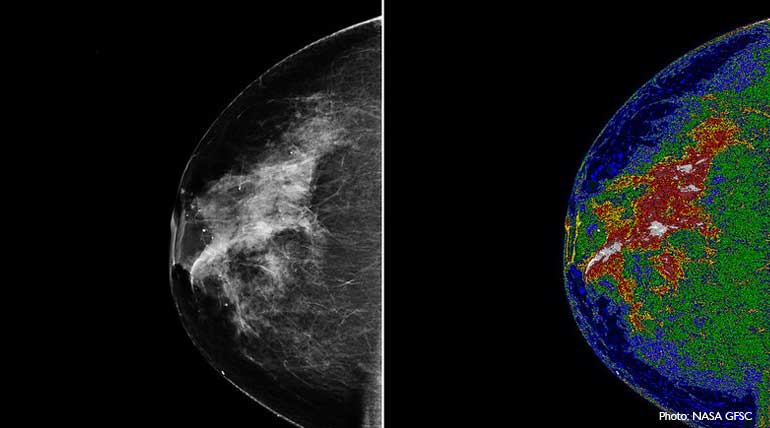

Tomosynthesis for women: With breast cancer for women on the rise, technology is lending a hand for its earlier deduction. One such new technology for testing breast cancer is Tomosynthesis or Tomo. It is a digital mammogram similar to the existing 2D digital mammography. But Tomo's advanced technology will capture images of the breast from multiple angles, unlike the 2D, which takes only two x-ray images, one from top to bottom and another from side to side angle.

Also, conventional 2D is limited by overlapping breast tissues. But with Tomo the x-ay tube moves in an arc over the compressed breast tissues to capture multiple images from different angles.  Since it ensures a complete and accurate scan, it can even identify cancer cells in thick breast tissues of women.

Then the images are reconstructed into a set of 3D images in a computer system.  The radiologist by examining the breast at multiple layers in depth will be better able to distinguish normal and tumor potential breast tissues.  Doctors confirm that it will detect breast cancer in earlier stages for providing better chances of beating cancer.